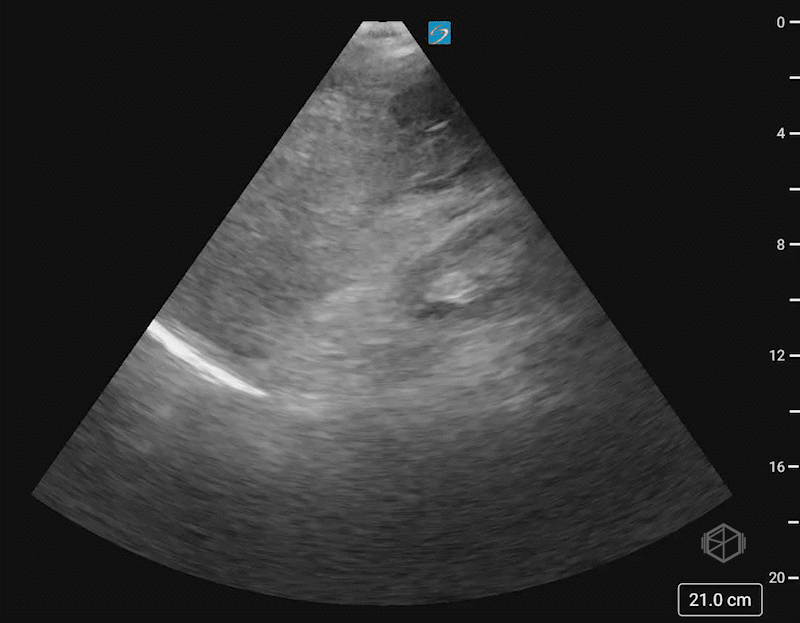

This was the patient’s FAST examination:

This FAST examination is clearly positive, with large amounts of complex fluid near the liver tip in the first clip. In the 2nd and 3rd clip, note the absence of the normal contour of the spleen. There is also free fluid at the tip of the spleen.

The patient had a CT that demonstrated AAST spleen grade grade 5 splenic injury based on active bleeding with hemoperitoneum and splenic laceration and left fourth through eighth rib fractures.

Diagnosis: Grade 5 splenic laceration with hemoperitoneum and active extravasation